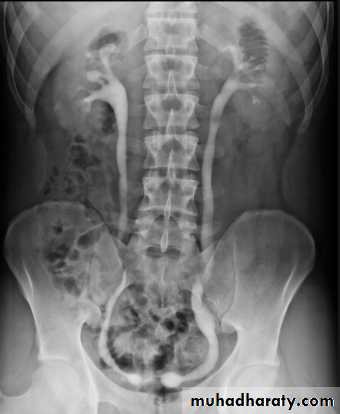

Horse shoe kidney -Kidneys may fail to separate.

-Almost invariably the lower poles remain fused.

-The kidneys axes are more parallel to the spine and malrotated.

-Diagnosis can be made by plain x-ray in some cases.

IVU shows

1. The kidneys at low position .

2.Close to the spine with long axis parallel to the spine .

3. Malrotation manifested by medially directed calyces.

4- The renal pelvis and ureters are anterior and lateral in position .